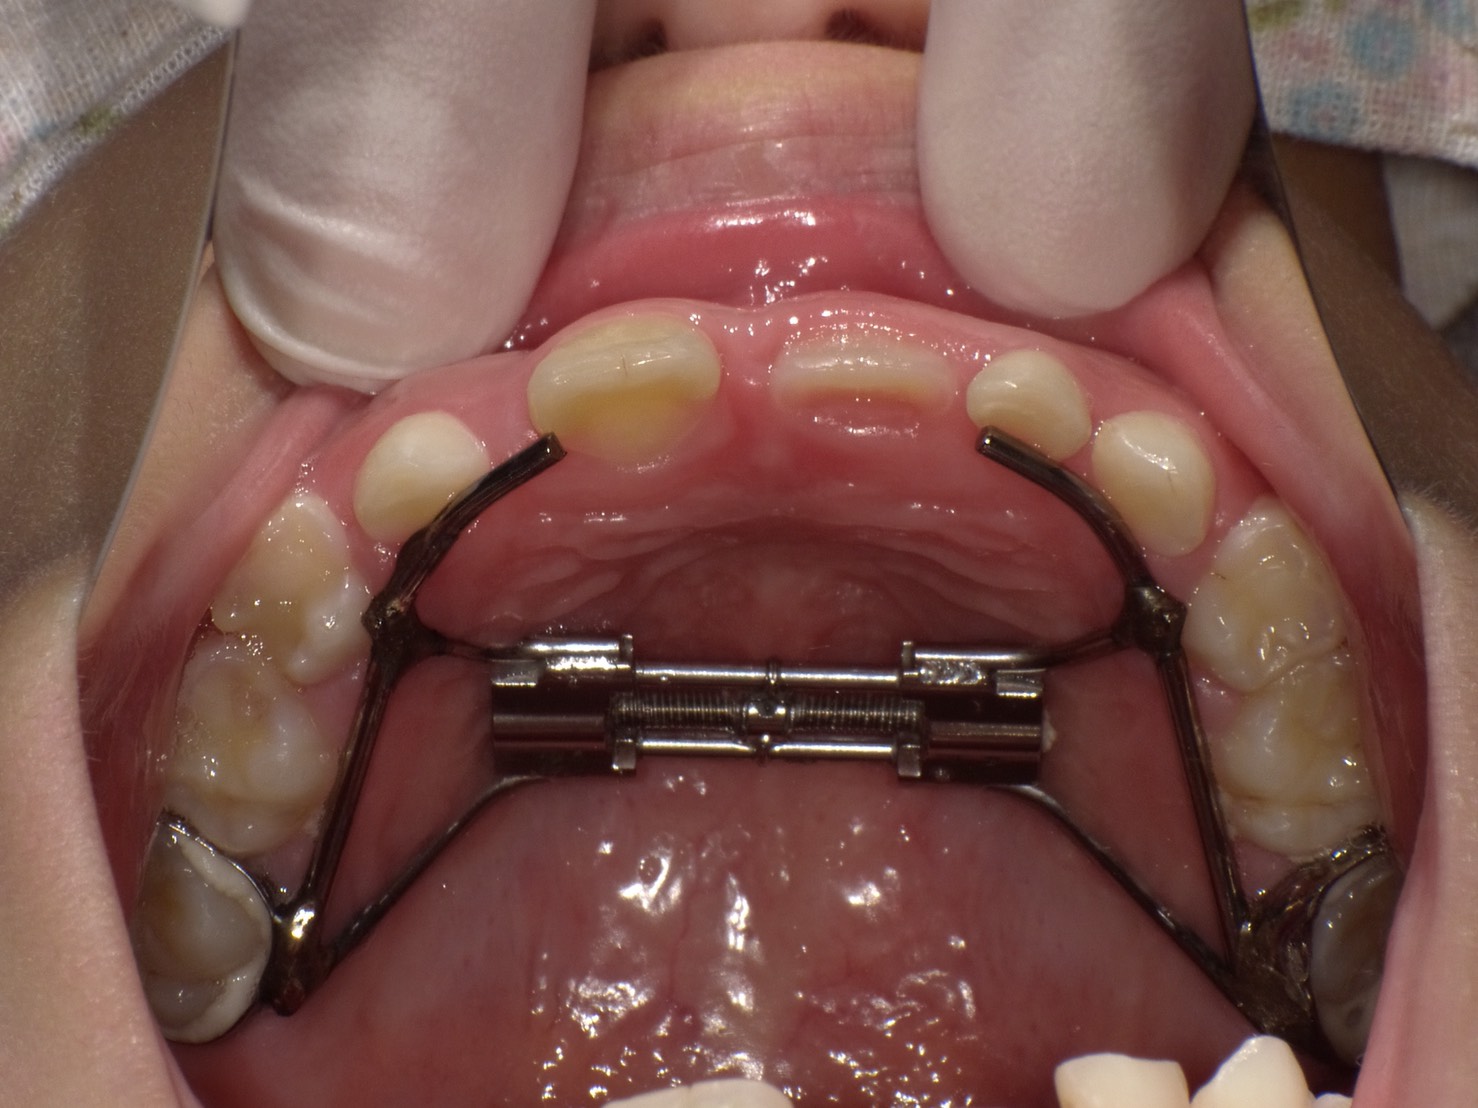

子どもの矯正・拡大床(小児矯正・第一期治療)

子どもの成長に合わせて歯並びを良くしていくために、乳歯から永久歯に生え変わる時期からの矯正治療です。急速拡大装置という固定式の装置と様々な装置を組み合わせて、子どものあごの成長に合わせて歯並びを良くしていきます。

小児矯正・第一期治療のメリット

- 抜歯しなくてよい

- 歯並びが悪いと、乳歯から永久歯に変わる時期に抜歯して永久歯が正常に生えるようにするリスクを低減できます。

こどもの矯正を始める時期について

お子様の歯並びや噛み合わせ等の状態によってことなりますが、おおよその目安としては6~8歳前後の早めの受診が望ましいです。ただ、凸凹、出歯などは8歳〜10歳ぐらいで開始しても問題ないケースも多いですが、気になる場合は早めにご相談ください。